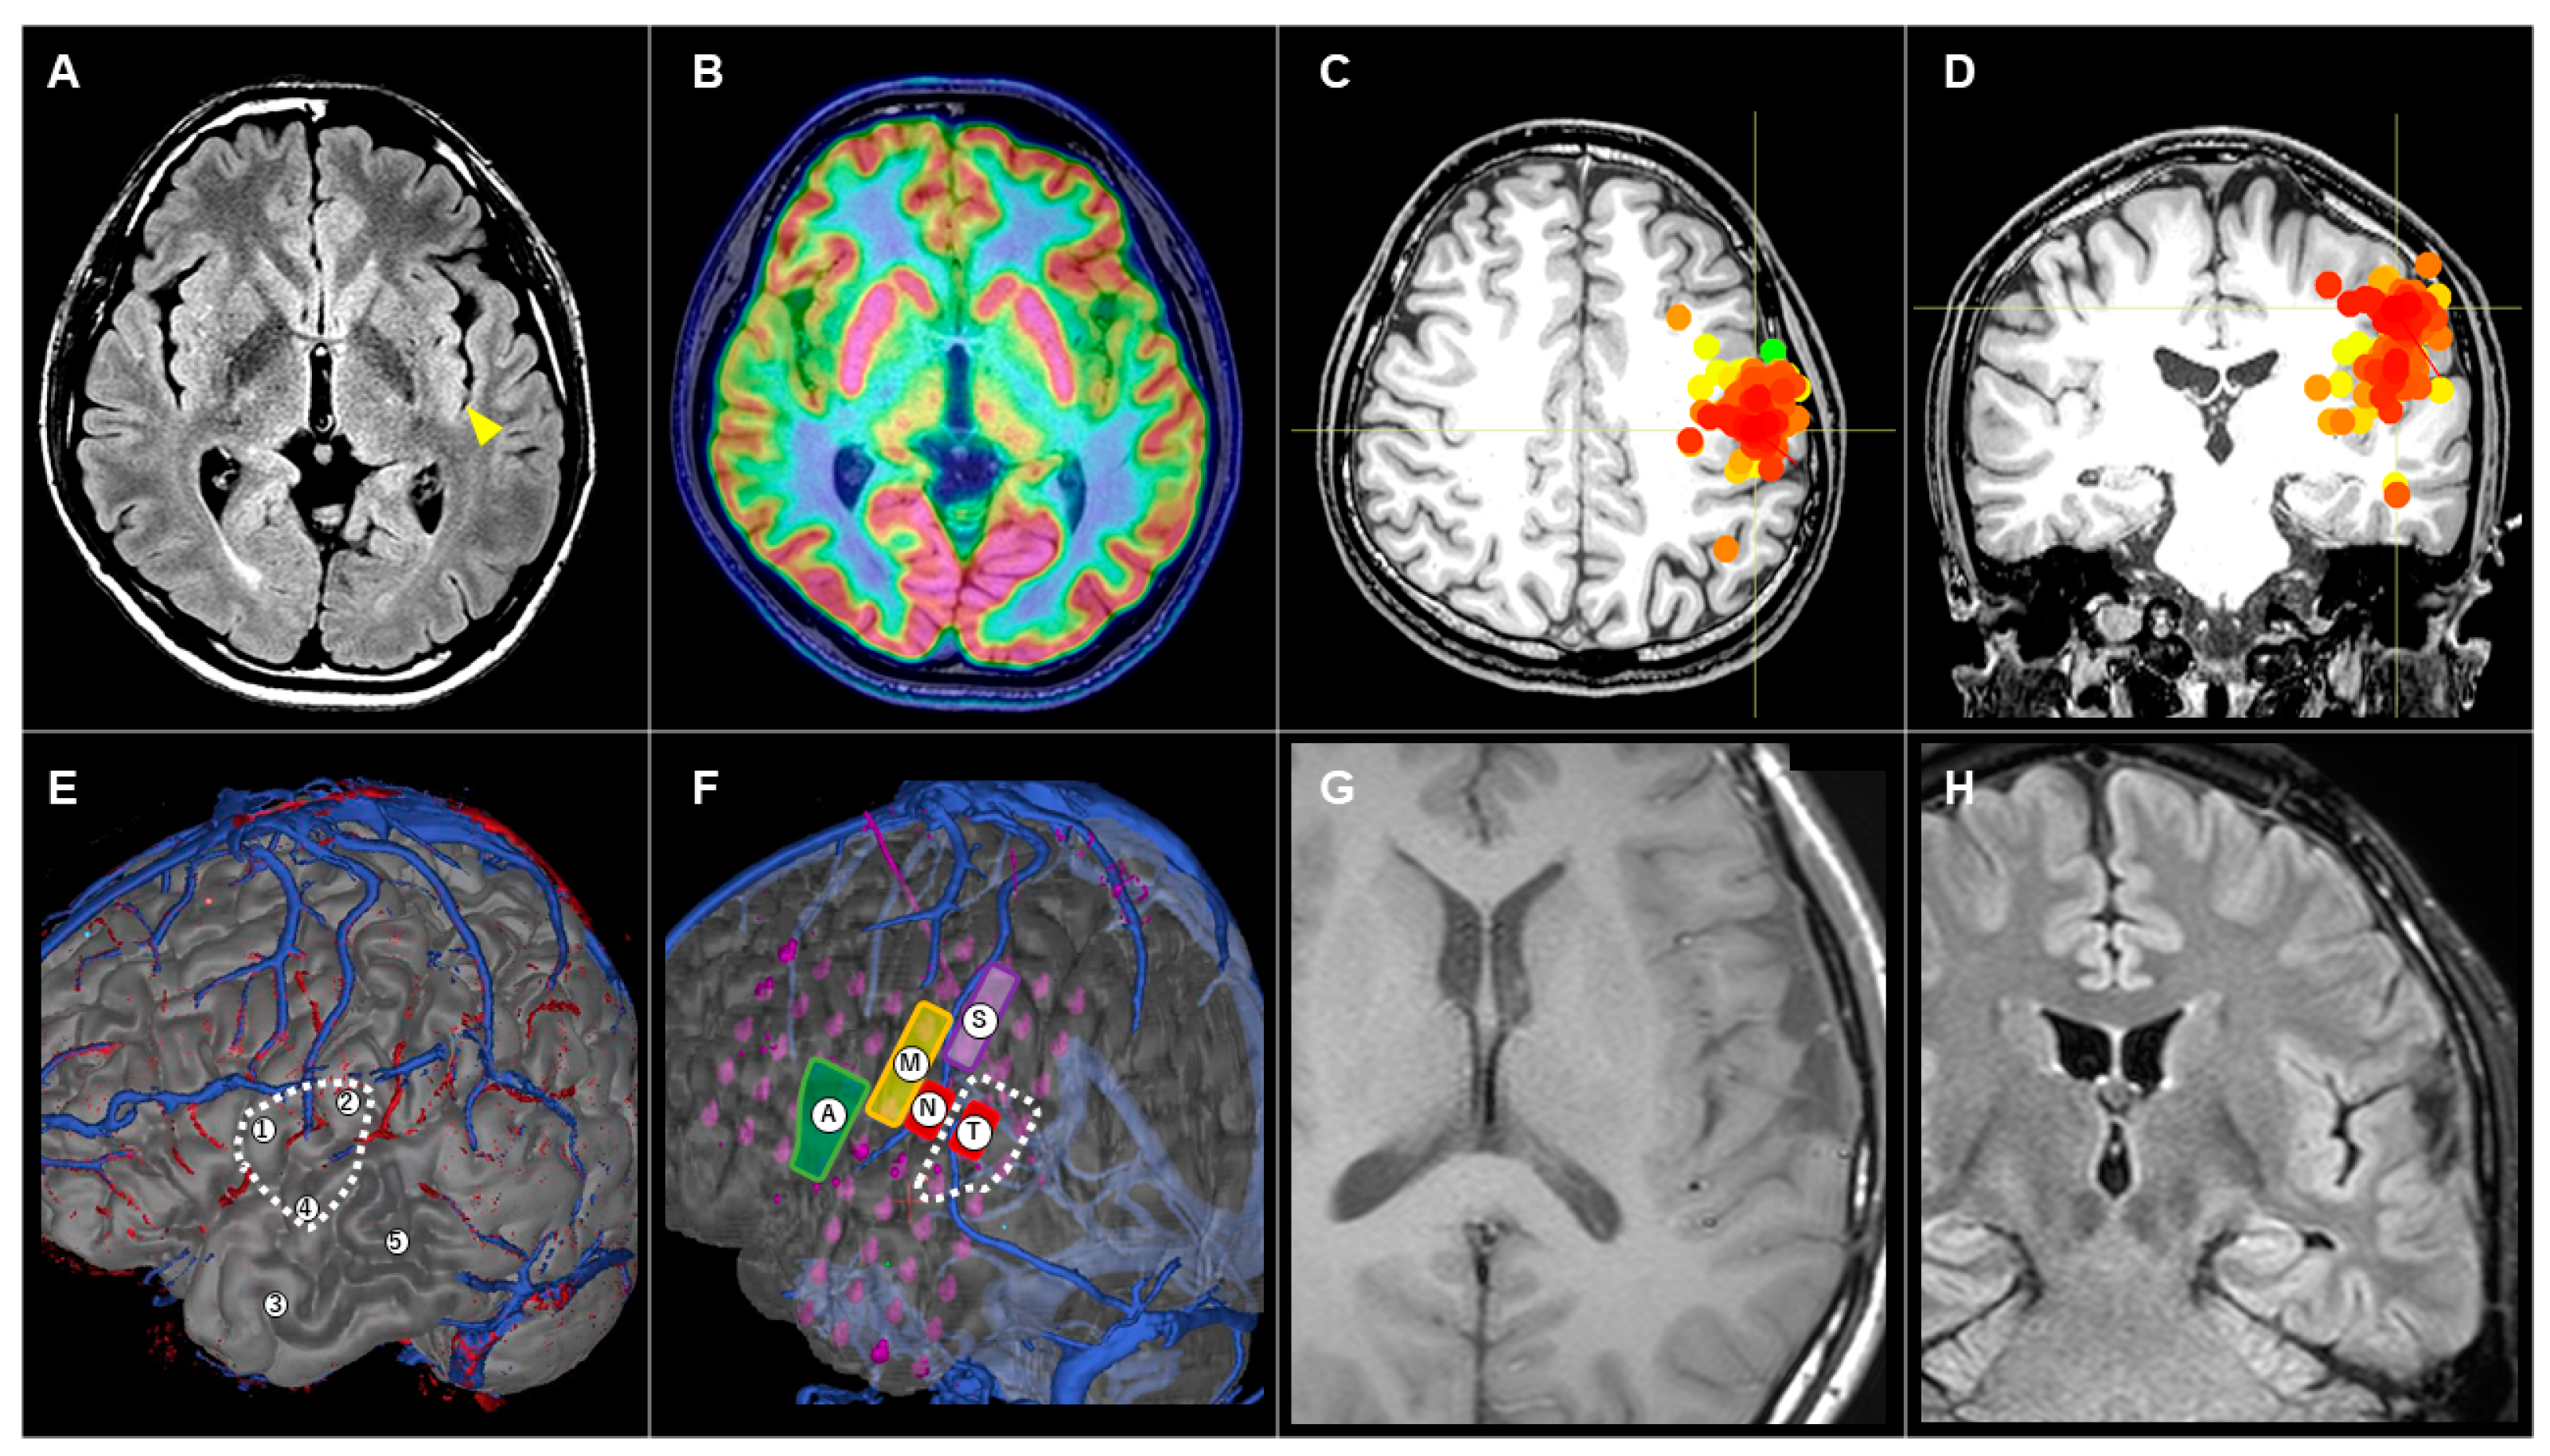

3.3.3. Patient #10 (AWC#3) (Figure 4)